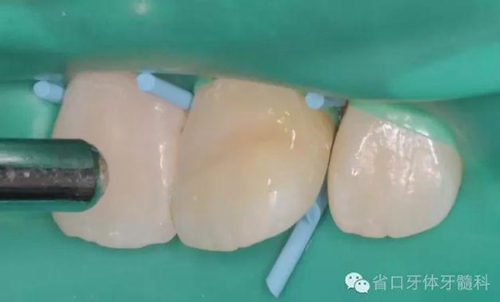

斷冠粘接前試對(duì)接

DUO-LINK樹(shù)脂水門(mén)?。˙ISCO)對(duì)位粘接,(牙齦紅腫,沒(méi)有安放橡皮障)

光固化,去除多余樹(shù)脂水門(mén)汀,近中鄰面洞和舌側(cè)開(kāi)髓孔樹(shù)脂充填,拋光,調(diào)整咬合。